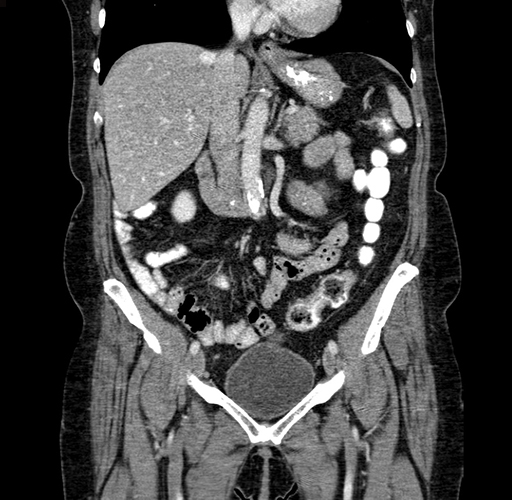

Axial Venous

Coronal Venous